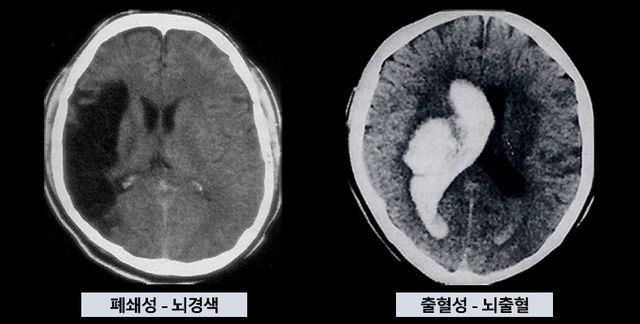

뇌경색과 뇌출혈 뇌경색과 뇌출혈

[에스포항병원 제공]